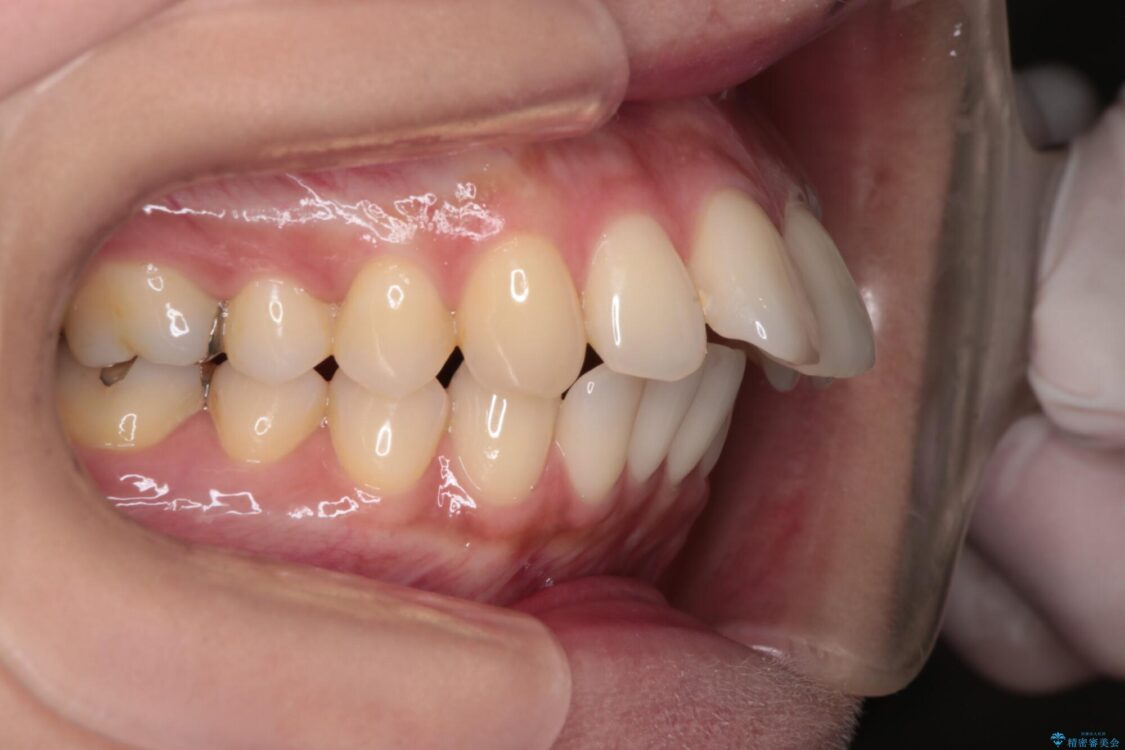

上の前歯の突出感を気にして来院された患者様です。

目立たない装置を希望とのことで、上顎左右第一小臼歯を抜歯し、インビザラインにて矯正治療を行うこととしました。

治療前

• 上顎前歯の突出を軽減 インビザラインによる抜歯矯正 治療前画像